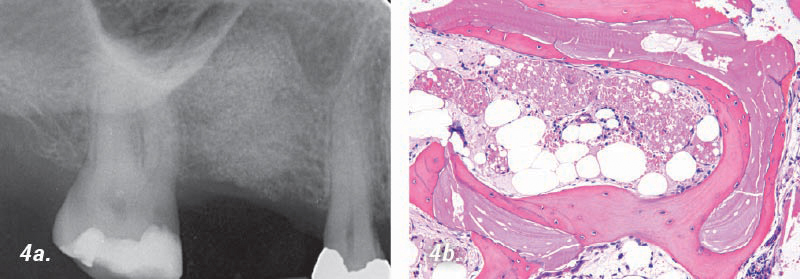

• 4a. 6 meses de postoperatorio: Se logró una altura ósea de aproximadamente de 14mm.

• 4b. Imagen histológica: La ilustración muestra hueso vital que rodea completamente al material de injerto.